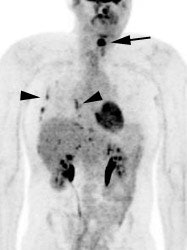

Metastatic head and neck cancer with secondary lung malignancy: The patient shown below had a history of head and neck cancer. The PET scan demonstrated a metastatic lesion to the right temporal bone. Also noted was intense uptake in the right lung apex(black arrow below right)- on CT this was felt to represent scarring (black arrowhead). FDG uptake is highly suggestive of a separate primary lung cancer. |

Recurrent head and neck cancer: The patient shown in the case below had a history of squamous cell carcinoma of the head and neck. The PET scan demonstrated focal tracer uptake in the left lower neck consistent with recurrent disease (black arrow on PET scan ,white arrow on CT). The PET scan also detected scattered foci of increased tracer activity within the right pleural space which corresponded to metastatic tumor implants (black arrow head on PET scan, white arrowhead on CT). |